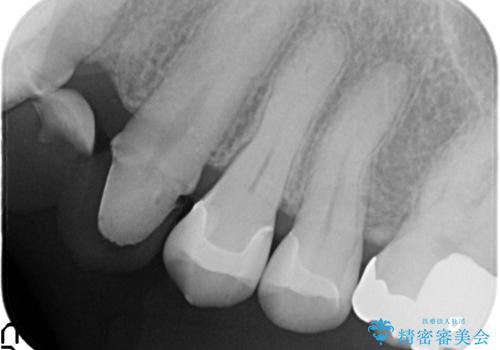

- 左上5番目の歯の銀歯が外れてしまったため、セラミックインレーによる修復を行った症例です。

手前の左上4番目の歯も虫歯だったため、セラミックインレーによる修復を行いました。

虫歯治療は虫歯の進行度によって処置が変わってきます。

虫歯が小さければ、インレー・クラウン等による修復・補綴処置を行うだけで済みます。

しかし虫歯が大きくなると神経処置や抜歯等をしなければならない場合もあります。